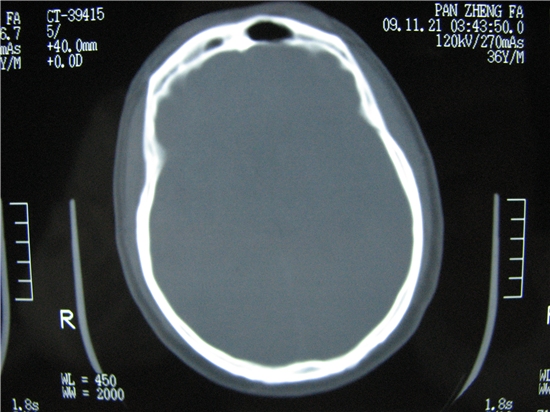

额窦里是什么,骨窗怎么不清晰,是不窗宽窗位的事。

额窦内及额部软组织内可见多发游离类骨质密度影,考虑额骨骨折可能。

额窦致密骨瘤,前额部及右顶部头皮损伤伴异物存留

左侧额骨、鼻骨骨折,头面部软组织肿胀。

左侧额骨、鼻骨骨折,额窦内的应该是游离骨块